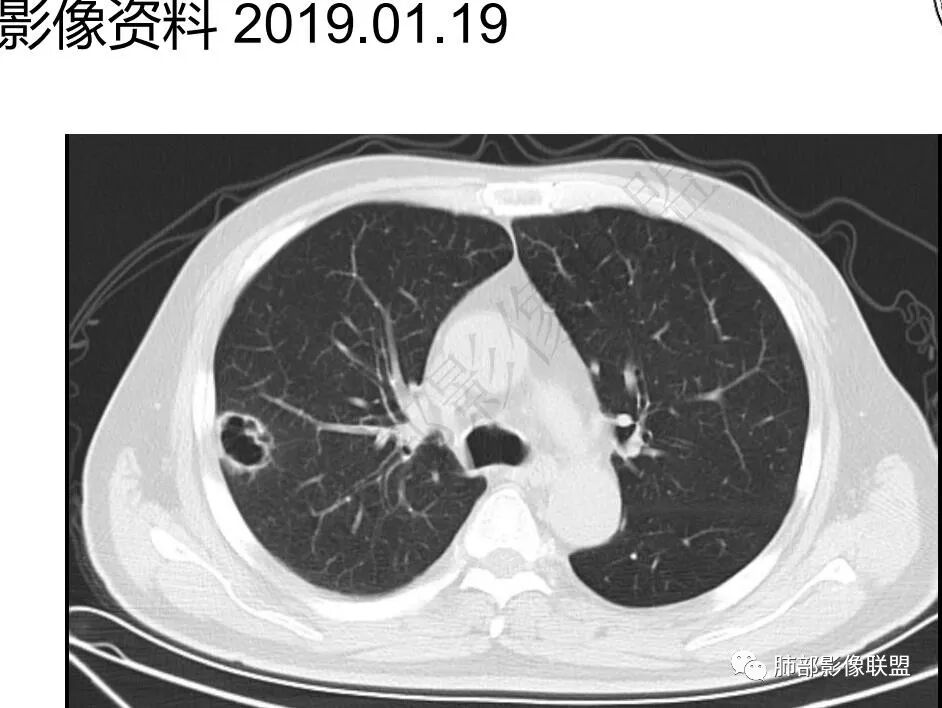

再1个多月后病灶继续增大,较明显不均匀强化,肺门一侧见低密度区。病灶边缘相对不清,可见毛刺。